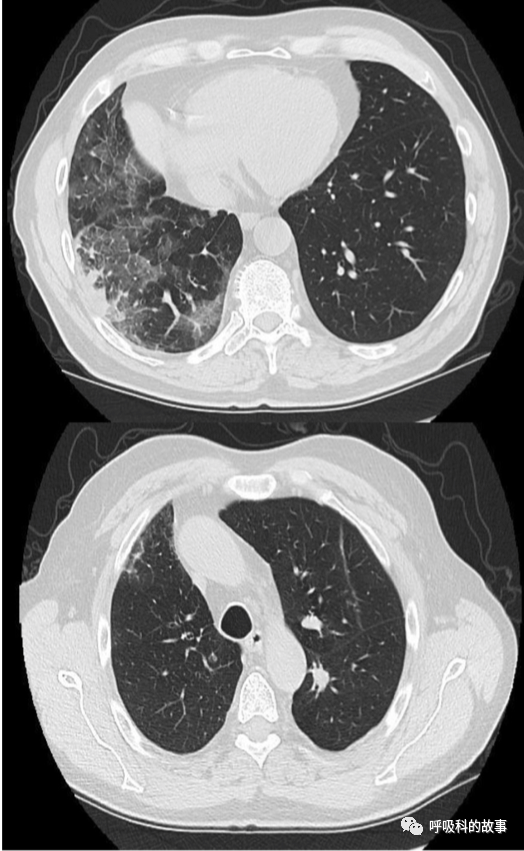

又過了三個月(發病後6個月),第三次胸部CT掃描顯示患者的縱隔內有一個10釐米的腫塊,右肺主動脈完全阻塞,上腔靜脈(SVC)部分塌陷(圖4)。